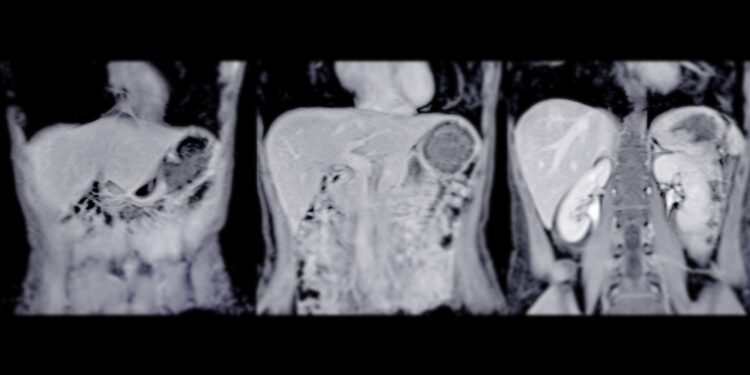

Pirmas žingsnis – pokalbis apie paciento savijautą, simptomus ir ligos istoriją. Toliau atliekama apžiūra ir papildomi tyrimai – dažniausiai skiriami vaizdiniai tyrimai, tokie kaip:

- Angiografija

- Kompiuterinė tomografija (KT)

- Magnetinio rezonanso tomografija (MRT)

- PET tyrimas

Diagnozės patikslinimui būtina atlikti biopsiją – paimama keletas audinių mėginių iš skirtingų naviko vietų ir jie tiriami laboratorijoje.